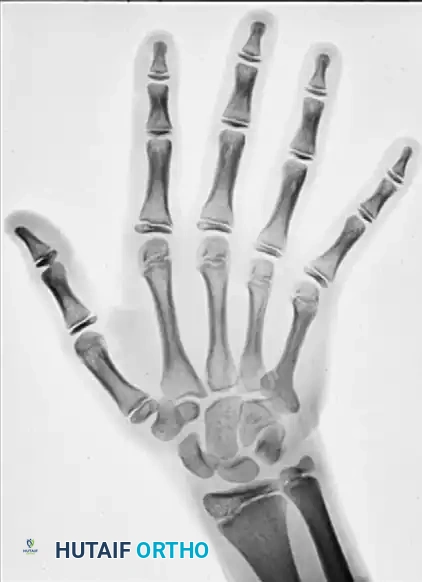

Radiographic presentation of an eccentric, ballooning lytic lesion characteristic of an aneurysmal bone cyst or aggressive osteoid osteoma variant in the proximal phalanx.

Radiographically, ABCs are almost indistinguishable from giant cell tumors or highly expansile enchondromas. They present as radiolucent, multiloculated ("soap bubble") lesions that cause tremendous cortical expansion, often reducing the cortex to a microscopic, eggshell-thin rim.

ABCs typically begin as eccentric, ballooning lesions located in the metaphysis of tubular bones (distinct from the epiphyseal location of giant cell tumors). As the lesion progresses, it enlarges to become centrally located, causing severe pain, swelling, and mechanical limitation of motion.